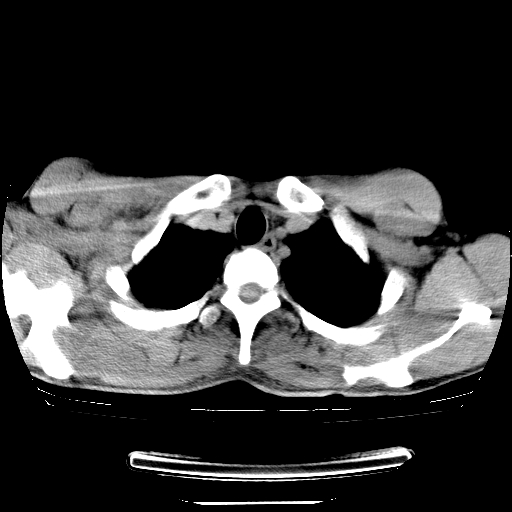

以下是引用dyqct在2008-4-29 8:43:00的发言:[br][br] 支持右侧胸腔包裹性积血。闭式引流管是不是插的太深了?

以下是引用zjzjr在2008-4-29 14:11:00的发言:[br]支持右侧胸腔包裹性积血。闭式引流管是不是插的太深了?胸腔引流,引流管快进入纵隔了.